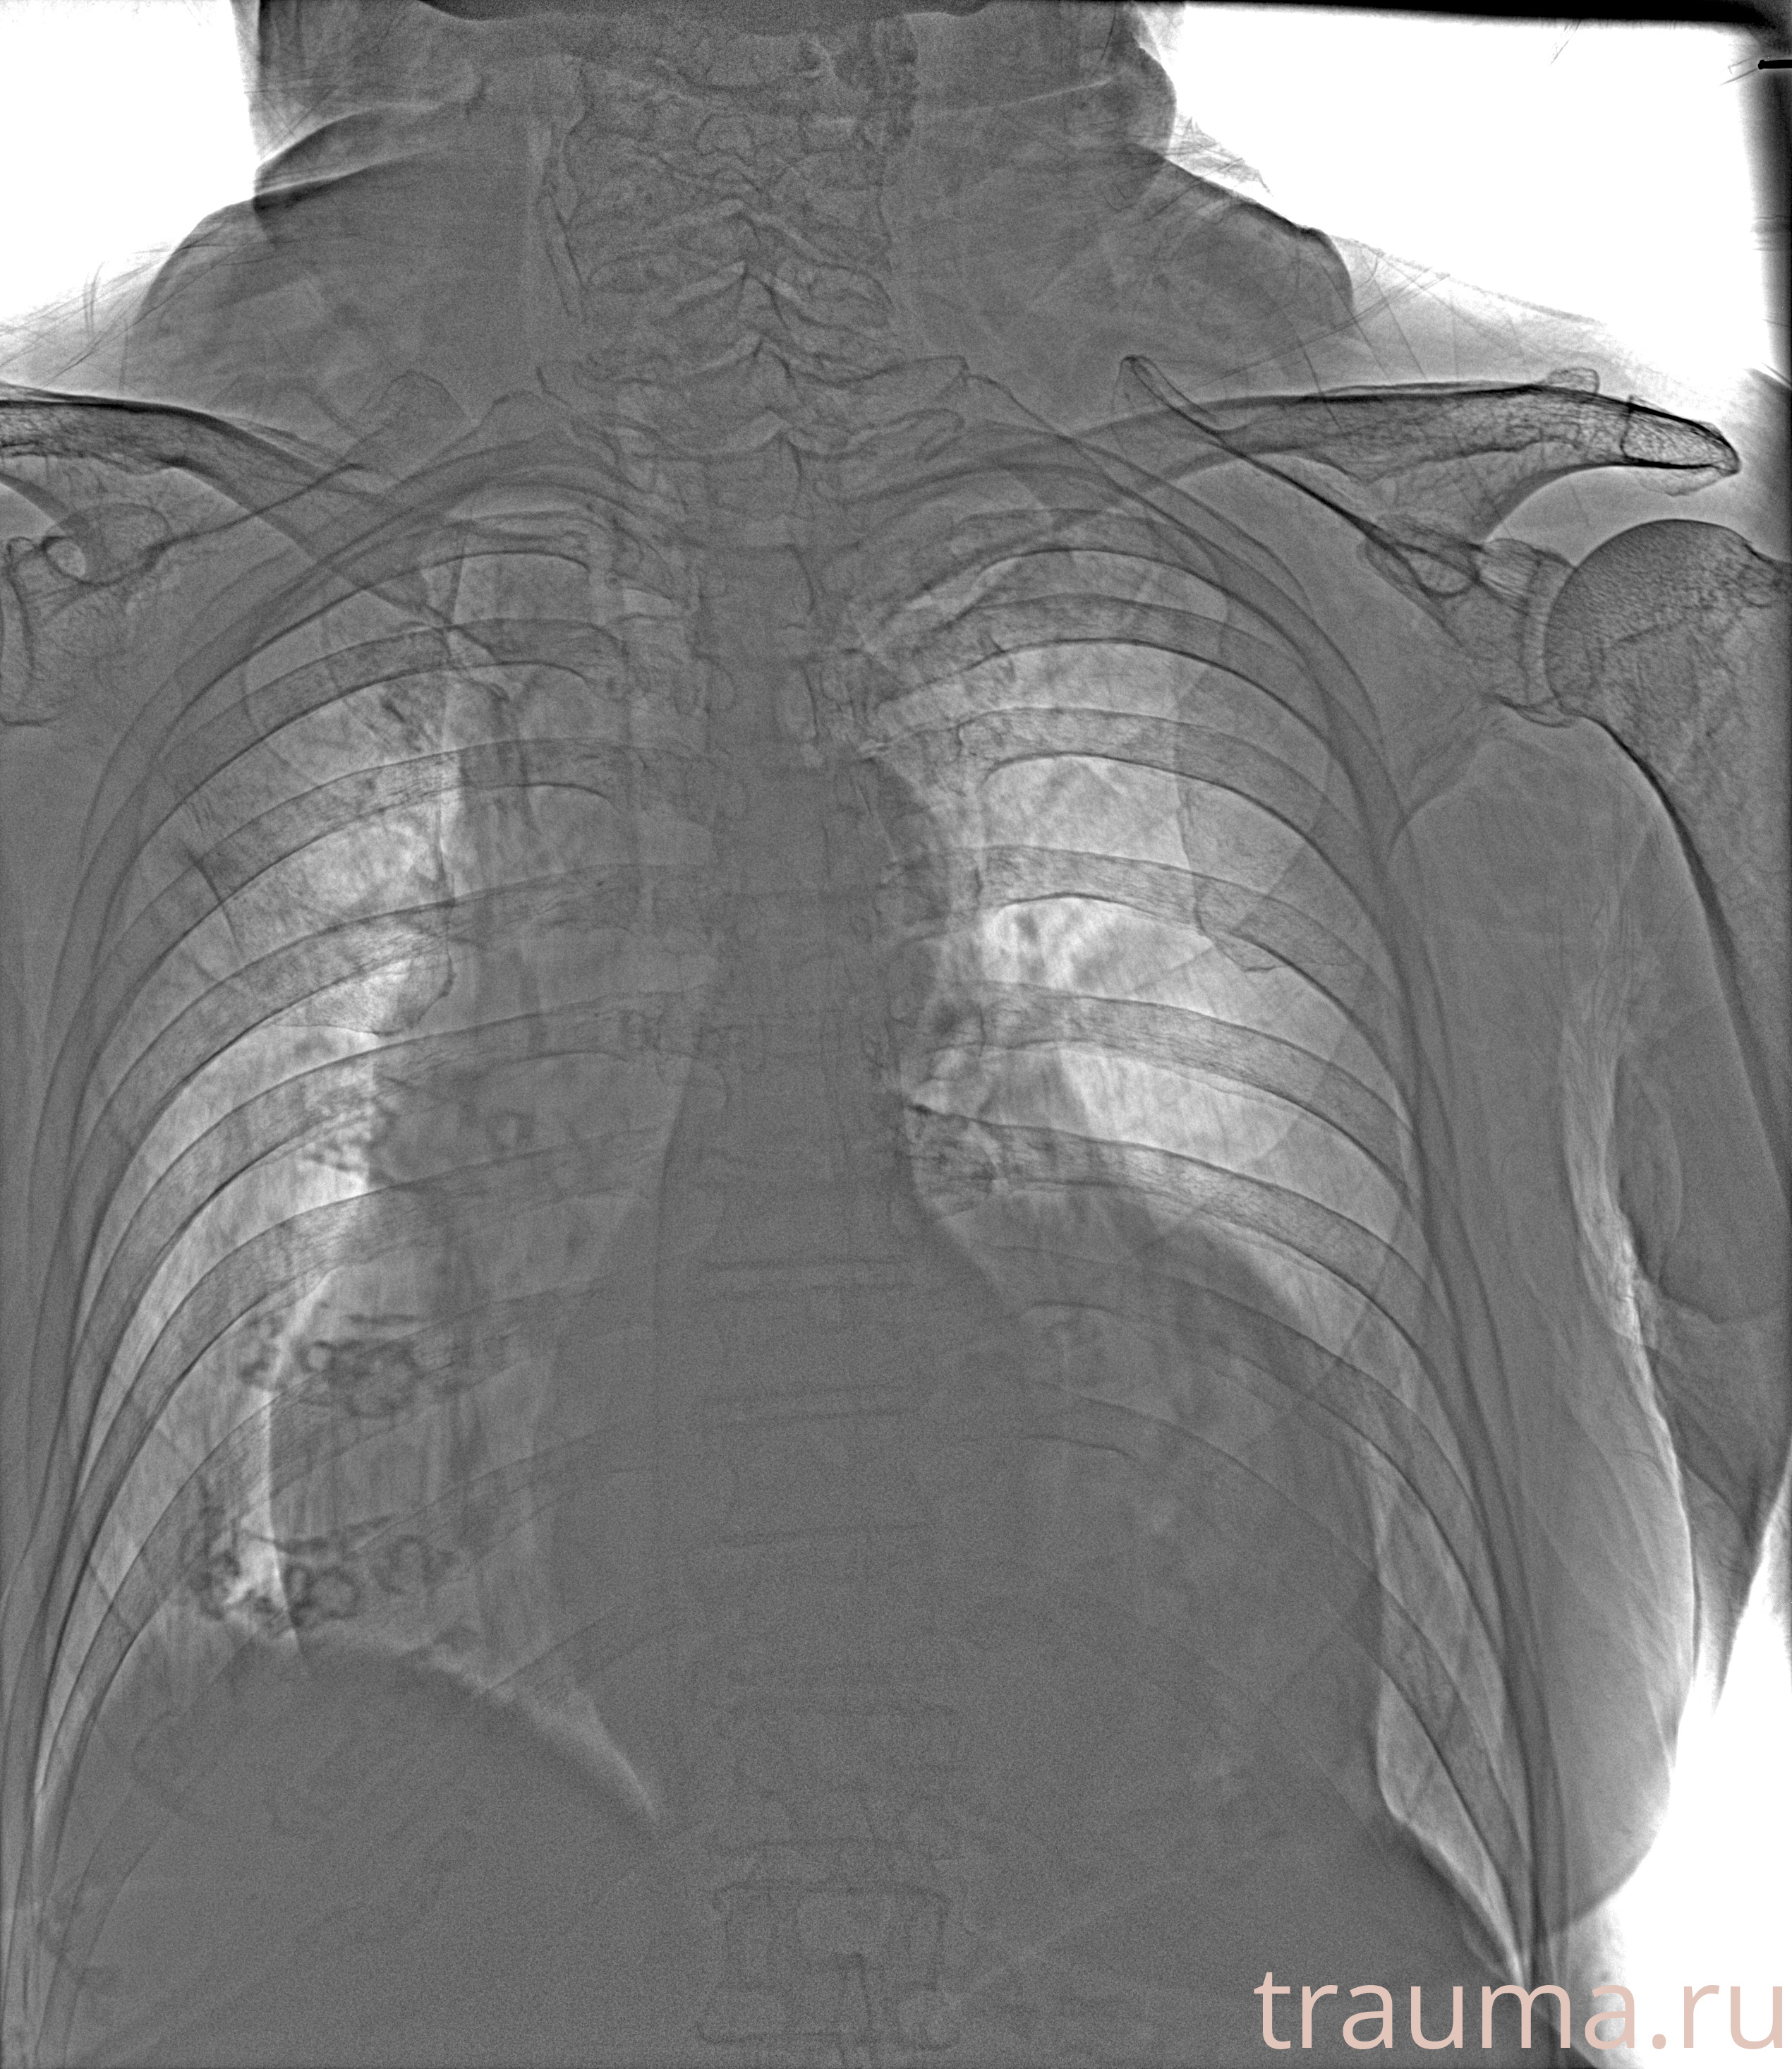

Рентген на дому: по вашему адресу приезжает врач-рентгенолог, травматолог-ортопед с мобильным рентгеновским аппаратом, проводит диагностику травмы или заболевания, делает необходимые рентгенограммы, дает рекомендации по дальнейшему лечению. Получить качественные снимки в домашних условиях возможно благодаря уникальной методике, разработанной МосРентген Центром для института  Склифосовского

при переломе шейки бедра и пневмонии от компании МосРентген Центр - партнера Института имени Склифосовского